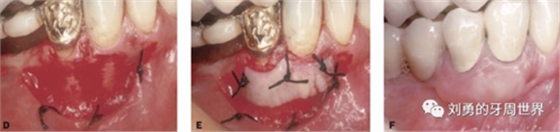

第四個要說的選擇就是受區(qū)翻開的半厚瓣可以有兩種處理方式,一種是根向移位縫合固定在根向的骨膜上,還有一種簡單的方式就是把這個半厚瓣剪掉扔掉。本人在臨床上喜歡兩個方法結合使用。

縫合方法的好處是受區(qū)可以更好的止血,但是缺點是操作困難,

剪掉方法的好處是操作簡單,但是缺點是增加受區(qū)出血。

比如下面兩張圖就分別是縫合和剪掉的方法: